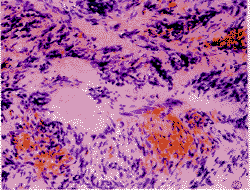

2.1,镜检,3例病变基本相同。肿瘤组织发生于淋巴结内,淋巴结被膜存在,边缘残存少量淋巴组织及淋巴窦,肿瘤中心未见残存淋巴组织,肿瘤组织周围形成假包膜,包膜较厚并有玻璃样变(图1)。肿瘤由梭形细胞组成,部分细胞细长,部分较肥胖,胞浆呈浅伊红色,胞界不清,核两端尖或圆钝,染色质细,核仁不明显,核周多有空泡,未见细胞异型及核分裂象。梭形细胞排列呈束状、编织状,部分呈栅栏状(图2)。在梭形细胞间可见圆形、椭圆形、短束状或不规则形胶原小结即石棉样纤维(图3),HE染色中呈伊红色,边缘多呈细星芒状,部分呈均质状或细颗粒状。早期胶原小结中心可见内衬单层内皮细胞的小血管,部分血管壁玻璃样变性(图4)。在例2中少数胶原小结中央有钙盐沉着(图5)。间质有出血,肿瘤边缘血管丰富,例2见弥漫性出血及含铁血黄素沉着,边缘有簇状发育不全血管。间质中炎症细胞少,无坏死,可见散在肥大细胞,部分胞浆透明,多分布于胶原小结周围。但例1中见灶状泡沫细胞、淋巴细胞浸润。Masson三色中AF中心呈绿色,其星芒状突起及肿瘤细胞呈红色;Van Gieson染色中AF呈红色,肿瘤细胞呈黄色。PAS染色见肿瘤细胞中糖原少或无。硫堇染色中见肥大细胞胞浆内颗粒呈棕红色。

图1 肿瘤组织边缘残存少量淋巴组织,周围形成假包膜,可见玻璃样变性。HE×200

图2 梭形细胞排列呈束状、编织状,部分呈栅栏状。梭形细胞间见嗜伊红石棉样纤维。HE×200

图3 短束状不规则形石棉样纤维位于梭形细胞间。HE×200

图4 早期石棉样纤维中心内衬单层内皮细胞的小血管,血管玻璃样变性。HE×400

图5 石棉样纤维呈细星芒状,部分中央有钙盐沉着。HE×200